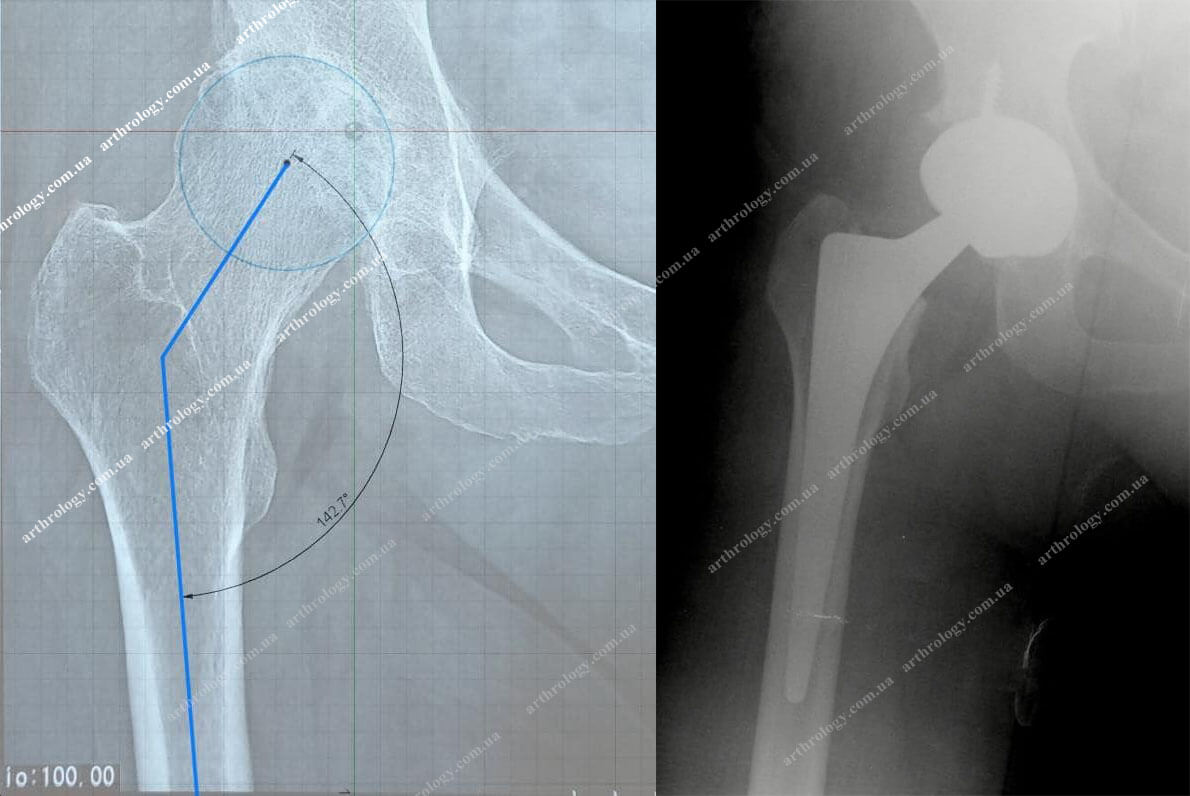

Иллюстрации и снимки, связанные с остеопенией шейки бедра